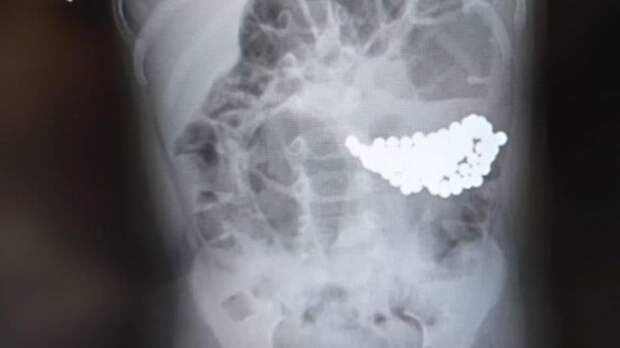

Хирурги извлекли из желудка годовалого мальчика 117 магнитных шариков

В Москве хирурги извлекли из желудка годовалого мальчика 117 магнитных шариков. Малыша экстренно доставили на операцию, после того как он поиграл под присмотром старшей сестры.

Обеспокоенные родители немедленно вызвали скорую помощь. После рентгеновского исследования девочку отправили домой, так как не заметили ничего подозрительного, а вот в желудке у ее брата собрался огромный ком из магнитных шариков.

"Специальными инструментами мы извлекли из желудка пациента аж 117 мелких инородных предметов. К счастью, магнитные шарики, притянувшись друг к другу, не успели нарушить функцию желудка", - приводит слова заведующего отделением гнойной хирургии № 2 Нодари Зурбаева пресс-служба столичного департамента здравоохранения.